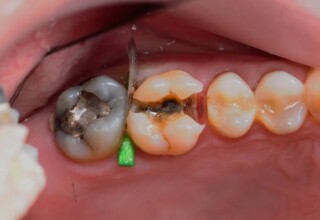

Posterior Tooth Root Canal Restoration with a Composite Resin Filling

The common restoration of a posterior tooth after a root canal is a crown. Its main purpose is to protect from fracture and concomitant extraction. In very few cases that specific criteria (mainly remaining tooth structure) are met or where finances predominate, an extensive composite filling can restore both aesthetics and function.

Restoration of a cracked molar with composite resin

Cracked teeth present a challenge in restorative dentistry both from the aspect of complexity of the restoration itself (usually large filings) and the necessary providings to avoid a complete fracture. The presented case demonstrates the simplest approach of a bonded direct restoration with composite resin. It is based on the principle of an adhesive filling that “holds” the remaining tooth structures “together”. The restored molar remained healthy for two years, then required a root canal and a crown was placed for maximum protection.